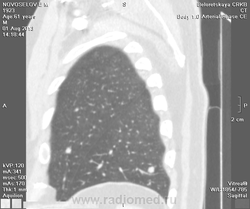

Мужчина оперирован по поводу BL щитовидной железы.Неоднократно проходил КТ в других лечебных учреждениях, у нас- впервые.Ставились заключения:MTS в лёгкие и лимф.узлы средостения слева.Образование слева увеличилось.Жалуется на одышку, не верит в заключение о MTS,просит узнать мнение других специалистов.

Метастазов в легкие не вижу. Похоже на лимфоузел в головке левого корня. Если позволите, запаздываете с началом исследования, плотность контраста в легочных артериях должна быть выше, чем а аорте. А одышка, не мудрено, легочная ткань диффузно уплотнена по типу "матового стекла", написал бы какую-нибудь интестициальную пневмонию, по типу альвеолита, может быть и гиперчуствительный пневмонит (не разберу есть или нет внутридольковые очажки), посмотреть бы изначально легочное окно, а не восстановленное из мягкотканного.

Кажется,я понял,что Вы имели ввиду.Очажки стрелочкой указал.Согласен с тем,что очаги на фоне отображеничя сосудов кажутся фантазией,но они присутствуют.

Коллега, вынужден извинться и дезавуировать свой первый пост. Пересмотрел. Да, есть очаги, и они - вероятнее всего, метастазы.